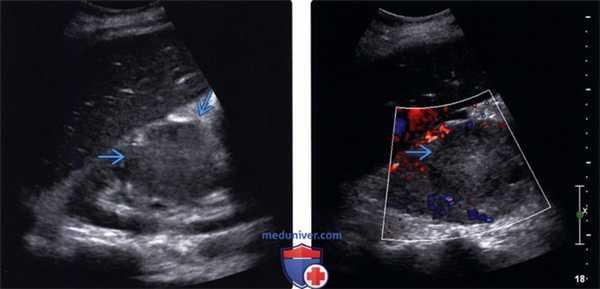

(Левый) На продольном ультразвуковом срезе в среднем отделе правой почки визуализируется солидное гомогенное, немного гиперэхогенное новообразование, представляющее собой метастаз меланомы, который невозможно отличить от почечноклеточного рака (ПКР).

(Правый) На соответствующем УЗ срезе с цветовой допплерографией визуализируется отсутствие выраженного кровотока внутри образования. Несмотря на то, что данные серошкального исследования неотличимы от ПКР, метастазы, по сравнению с ПКР обычно более гиповаскулярны.